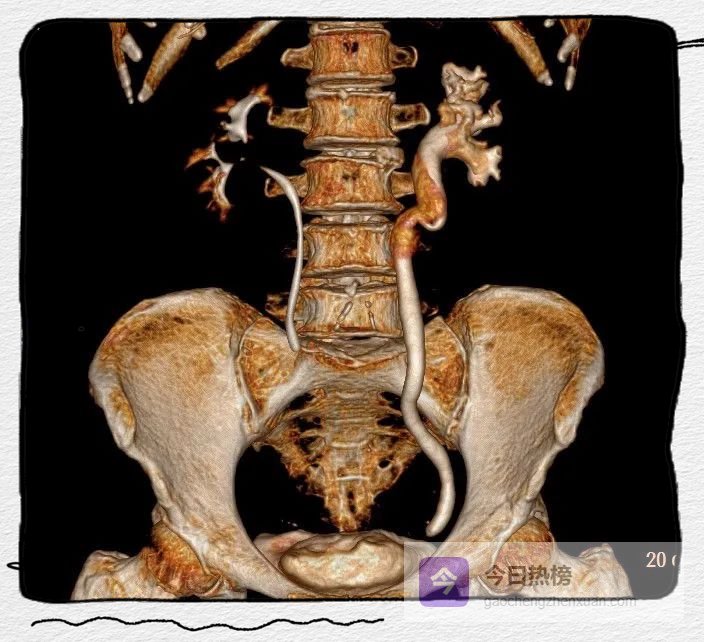

图4A-C

左侧肾盂及输尿管上段呈“双环及双腔样”改变,考虑夹层形成;三维重建可清楚的观察到撕裂肾盂及输尿管的真假腔并显示撕裂范围。